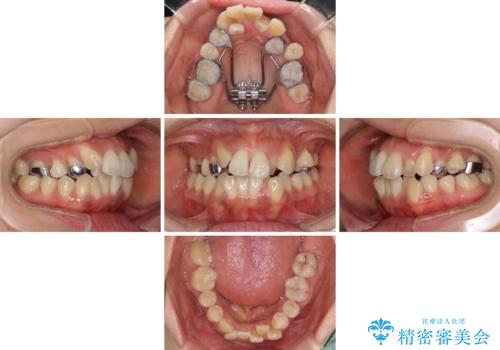

狭い上顎骨を拡大 著しい叢生を抜歯矯正で改善

- 上顎の著しい叢生と奥歯の咬みにくさを気にして来院された患者様です。

骨格的に上顎は狭く、下顎は右側にシフトしていたため、右側臼歯はクロスバイトとなっていました。

上顎骨を急速拡大装置により拡大し、ワイヤー装置による抜歯矯正治療を行うこととしました。